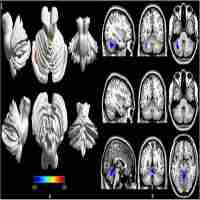

| Description | Journal: Brain and Behavior Neuroimaging studies can shed light on the neurobiological underpinnings of autism spectrum disorders (ASD). Studies of the resting brain have shown both altered baseline metabolism from PET/SPECT and altered functional connectivity (FC) of intrinsic brain networks based on resting-state fMRI. To date, however, no study has investigated these two physiological parameters of resting brain function jointly, or explored the relationship between these measures and ASD symptom severity. Here, we used pseudo-continuous arterial spin labeling with 3D background-suppressed GRASE to assess resting cerebral blood flow (CBF) and FC in 17 youth with ASD and 22 matched typically developing (TD) children. A pattern of altered resting perfusion was found in ASD versus TD children including frontotemporal hyperperfusion and hypoperfusion in the dorsal anterior cingulate cortex. We found increased local FC in the anterior module of the default mode network (DMN) accompanied by decreased CBF in the same area. In our cohort, both alterations were associated with greater social impairments as assessed with the Social Responsiveness Scale (SRS-total T scores). While FC was correlated with CBF in TD children, this association between FC and baseline perfusion was disrupted in children with ASD. Furthermore, there was reduced long-range FC between anterior and posterior modules of the DMN in children with ASD. Taken together, the findings of this study – the first to jointly assess resting CBF and FC in ASD – highlight new avenues for identifying novel imaging markers of ASD symptomatology. |